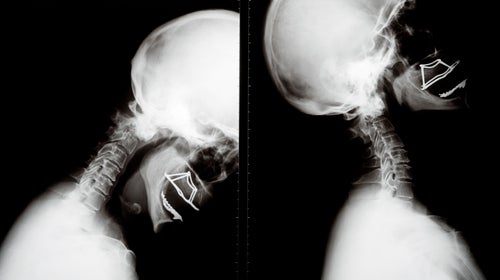

The physiology of a hit is pretty simple. It begins, for example, with you falling off your bike, snowboard, or skateboard. As you鈥檙e flying toward the ground, your brain is floating inside your skull, suspended in a layer of clear, colorless fluid, like a bowl of Jell-O that hasn鈥檛 quite set around the edges. When impact occurs, it鈥檚 the shaking of the brain inside your skull that causes the concussion. 鈥淭hat force鈥攖he banging, the twisting, the rotation, the acceleration and deceleration鈥攄eforms the brain and causes damage to the neurons and other cells that help the brain function,鈥 Stein says. Initially, you may or may not lose consciousness. Later you might experience memory loss, nausea, equilibrium problems, or headaches鈥攕ometimes for weeks, sometimes for months.

The damage you sustained鈥攁nd any further injury after that, especially before the brain has fully healed鈥攃an lead to problems with the transport of proteins in the brain, the same way potholes might impede the smooth flow of traffic on a city street. In fact, this metaphor is nearly literal. As Stein slices the brain he is working on, he shows me spots where trauma created visible gaps in the tissue.聽

Stein also says that an athlete doesn鈥檛 need to take a direct hit to the head to incur damage. 鈥淪ports where riders make these big landings could cause problems,鈥 he says. 鈥淭hey鈥檙e 20 feet in the air, and their brain is falling at high velocity, just like their body. When they stop, the brain keeps moving inside the skull. They don鈥檛 have to have pain. They don鈥檛 have to say ouch.鈥

Stein, McKee, and their colleagues have identified four stages of CTE. In the first, tau protein builds up, mostly in the brain鈥檚 frontal lobe. As levels of tau increase in stage two, pathways in the brain called microtubules become twisted. Then they collapse, degenerating into neurofibulary tangles, effectively acting as roadblocks to normal function. It鈥檚 in stage two that symptoms like aggression, depression, and impulsiveness begin to appear. In stage three, as the tau spreads, the most essential parts of the brain鈥攖he mood, memory, and learning聽controlling amygdala and hippocampus鈥攍ose function. By stage four, the brain is overloaded with tau deposits, sometimes shrinking to half its original size. Ultimately, it can no longer perform the basic functions required for life.聽